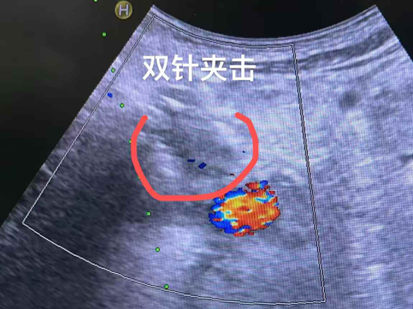

經過多學科會診,醫療四科團隊為佢實施咗胰臟腫瘤納米刀消融術+腹腔神經叢阻滯術,術後配合免疫治療,喺控制腫瘤嘅同時有效緩解癌痛。

「納米刀消融唔到一個鐘就完成咗。」莫林回憶道,呢個同佢最初聽到嘅「八個鐘」完全唔同。即使喺ICU觀察嗰一晚,醫護人員嘅陪伴都令佢感到非常安心。術後幾日,奇蹟慢慢出現:佢重新有胃口、可以安睡,體重亦開始回升。之後,莫林再接受咗動脈灌注化療。